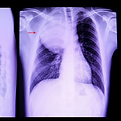

Intervención quirúrgica en pulmones.

Nódulos pulmonares

Tumores pulmonares

Enfisema y bullas pulmonares

Infecciones y secuelas pulmonares